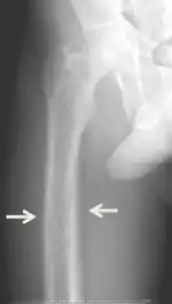

Los síntomas inespecíficos incluyen sensación de cansancio y sed, existen cambios de humor que incluyen, tristeza, debilidad y irritación junto con otros síntomas como el picor, dolor de cabeza, dolor articular, olvido y dolor abdominal.[8][4][9][1] Los síntomas más específicos relacionados con los niveles de calcio y fosfato elevados en sangre incluyen dolor de huesos (osteodinia) y sensibilidad ósea que son comunes y están relacionados con sensibilidad de músculo proximal. Otros signos pueden incluir pancreatitis, piedras de riñón, calcificaciones corneales, adelgazamiento de huesos largos y calcificaciones hipodérmicas que pueden ser palpables en algunos pacientes.[2]

El diagnóstico incluye análisis tanto clínicas como de laboratorio. Las investigaciones radiológicas buscan signos de pérdida de hueso en manos y pelvis, rasgo característico hiperparatiroidismo terciario.[8] Otro examen clínico puede incluir la clasificación de la debilidad muscular, que se realiza pidiendo al paciente que se ponga de pie desde una posición sentada con las manos cruzadas sobre el pecho.[4] Los análisis de laboratorio incluyen determinación del nivel de calcio de sangre y de fosfatasa alcalina, los cuales están siempre aumentados en el hiperparatiroidismo terciario. Otros resultados comunes de laboratorio incluirían niveles disminuidos de vitamina D, hormona paratiroidea elevada de sangre elevada e hiperfosfatemia.[9][1]